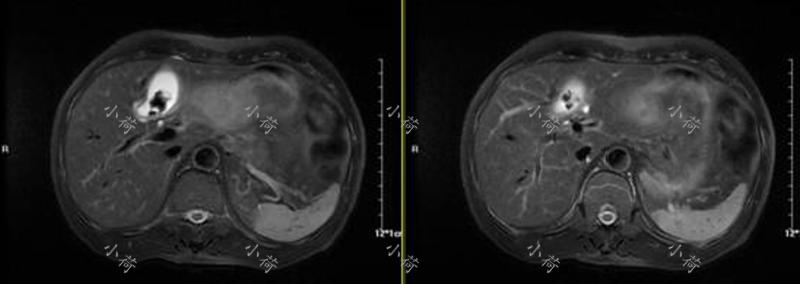

这是5个月前第一次见到患者时的情景,患者带着以前检查的结果,一再肯定地说自己胆囊炎发作了,让我们赶紧给他输抗生素治疗,患者2年前的腹部MRI示:胆囊内见多发不规则充盈缺损影,胆囊体积增大,肝内、外胆管未见扩张,其内未见充盈缺损影,余未见明确异常(图1)。肿瘤标志物结果回报:CA-199:1428.0 U/mL、AFP+CEA+CA153+CA125:均正常。CA-199如此之高,绝不是胆囊炎这么简单,看来要摊上大事了!

图1 腹部MRI提示胆囊多发结石、胆囊炎